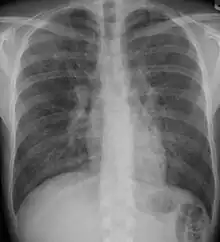

![]() | |

| End-stage pulmonary fibrosis of unknown origin, taken from an autopsy | |